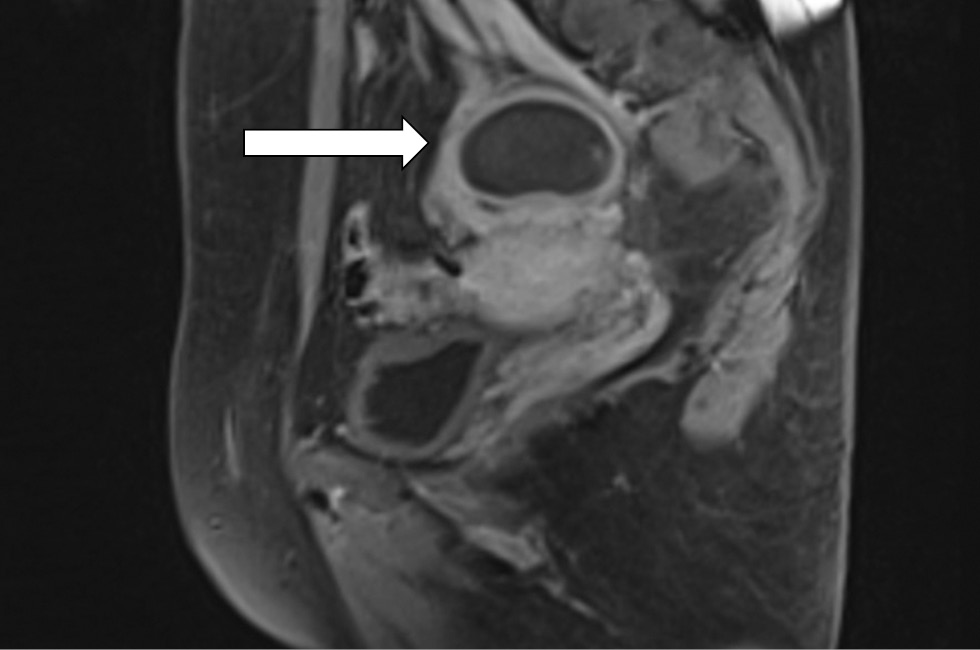

MR-presentation of adenomyosis was concluded based on the magnetic resonance imaging from 06/01/20. Ovarian cancer was questionable, as well as bilateral ovarian endometriomas and lymphadenopathy. Multiple uterine fibroids were of small size (Fig. 3–5).

Fig. 3. Magnetic resonance imaging of the pelvis on admission. The left ovary contains a multi-chambered formation with parietal components and finely dispersed contents (arrow)